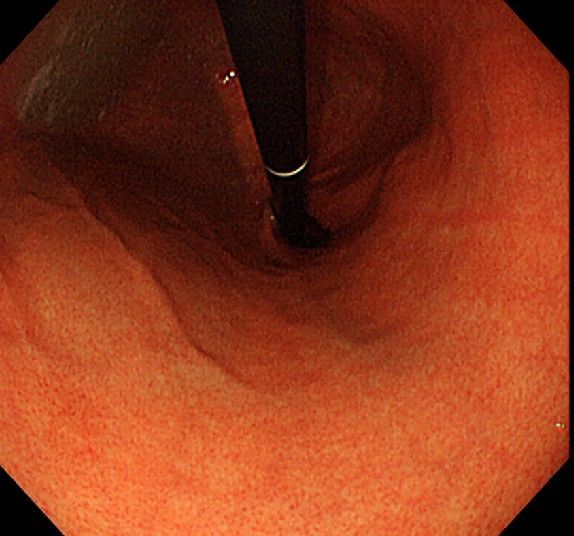

위 내시경을 찍었는데 위염 종류 사진을 알 수 있을까요? (사진 많습니다..)

한달 전 쯤에 소화불량과 속쓰림이 3개월 동안 약을 먹어도 낫지 않아 위 내시경을 찍었는데 위에 염증이 많이 있다는 이야기를 들었습니다...그런데 상태가 얼마나 안 좋은지 어떤 종류의 위염인지에 대해서는 물어봐도 안 알려주셔서 여기에라도 올려서 여쭈어봅니다... 제 상태가 얼마나 심각한 걸까요..

사진상으로 보아서는 정상에 가까운 점막상태이거나 약간의 표재성 위염이 있는 정도로 보입니다.

홍반성 위염이 있으며 경증의 역류성 식도염이 있습니다

위내시경상으로는 특이소견이 없다고 보셔도 됩니다